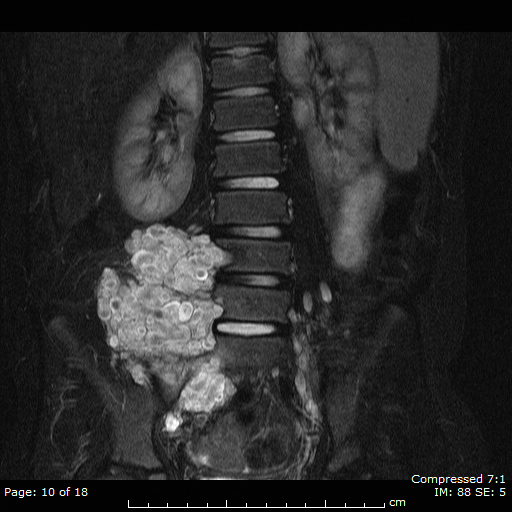

Plexiform Neurofibroma